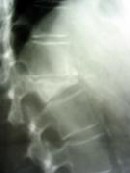

Störungen im Knochenabbau: Machen Knochen instabil, lassen Nervenzellen sterben und können zu Erblindung führen (Foto: Uni Würzbürg)

Störungen im Knochenabbau führen zu Osteopetrose. Dabei handelt es sich um eine schwere Erbkrankheit, bei der Knochen zu dicht und deshalb instabil werden - sozusagen das Gegenteil der im Alter häufigen Osteoporose. Bei manchen Patienten kommt es gleichzeitig zum Untergang von Nervenzellen und zur Erblindung.

Ein Forscherteam aus der Arbeitsgruppe von Prof. Dr. Dr. Thomas J. Jentsch am Zentrum für Molekulare Neurobiologie (ZMNH) der Universität Hamburg hat herausgefunden, dass das Zusammenspiel zweier Proteine essentiell für den Abbau von Knochensubstanz ist.

Dabei handelt es sich um die Proteine ClC-7 und Ostm1. Das Protein Ostm1 bildet einen molekularen Komplex mit dem Protein ClC-7, dessen Funktion der Transport von Chlorid-Ionen über die Zellwände ist. Beide Proteine zusammen erreichen die Lysosomen, die für den Abbau und das Recycling nicht mehr verwendeter Zellbestandteile verantwortlich sind.

Außerdem finden sich Ostm1 und ClC-7 in Osteoklasten, den für den Abbau von Knochen spezialisierten Zellen. Ohne seinen Partner Ostm1 wird der Chloridtransporter ClC-7 instabil. In der Folge funktionieren das zelluläre Recycling und der Abbau von Knochen nicht mehr. So genanntes Speichermaterial ("Zellmüll") sammelt sich an, worunter die Körperzellen leiden.

Einige von ihnen, zum Beispiel im Gehirn, können sogar absterben. Die Knochendichte nimmt erheblich zu. Mäuse, denen entweder das Protein Ostm1 oder ClC-7 fehlt, haben zu dichte Knochen, sind blind, verlieren bestimmte Nervenzellen und haben zudem graue Haare. Der Effekt auf die Haarfarbe ist noch völlig unverstanden, aber auch hier liegt die Lösung vermutlich im Zusammenspiel von Ostm1 und ClC-7.